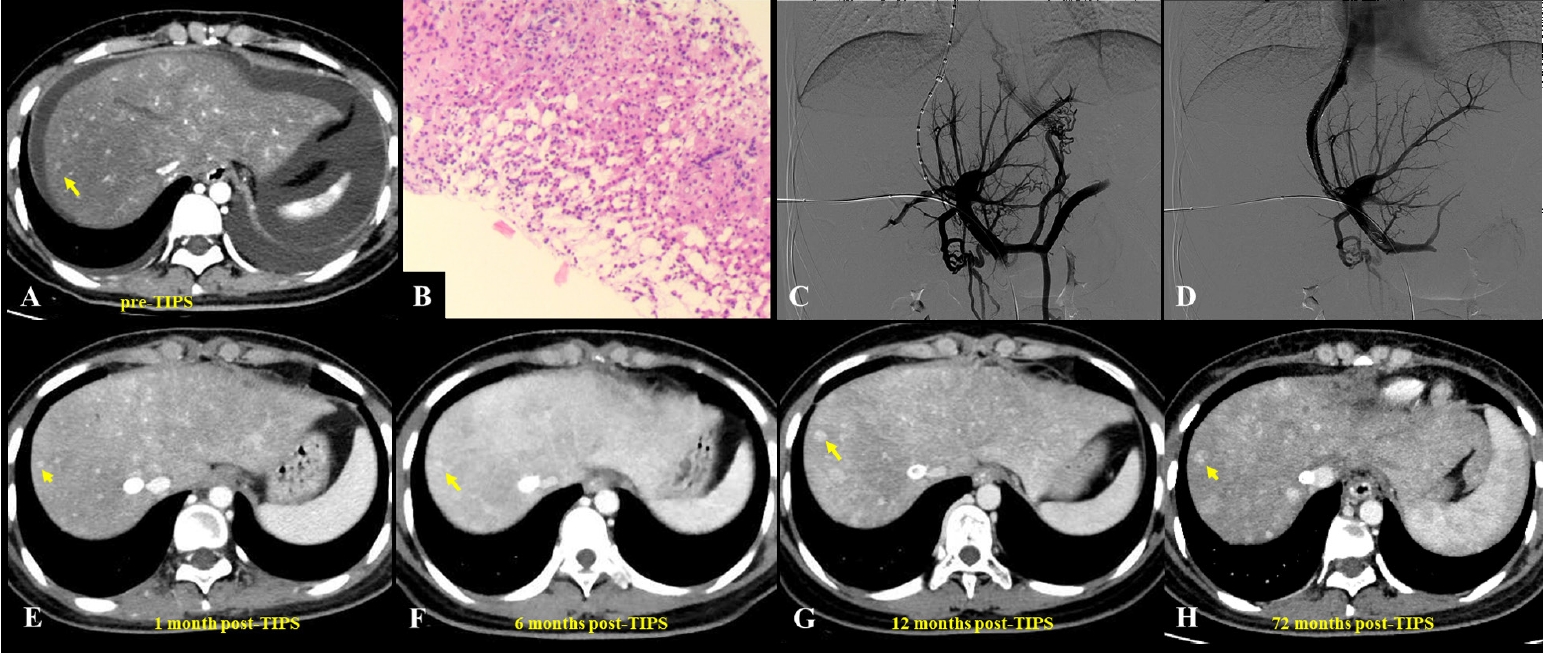

Fig. 1.A 62-year-old man diagnosed with hepatic sinusoidal obstruction syndrome 4 months after ingestion of Gynura segetum. (A) Abdominal computed tomography (CT) during the hepatic venous phase demonstrated patchy parenchymal enhancement with characteristic clover-like enhancement around the hepatic veins. Significant ascites and bilateral pleural effusions were also observed. (B) Coronal CT revealed patchy liver enhancement and narrowing (thinning) of the portal vein, accompanied by abundant ascites. (C, D) Portography before and after transjugular intrahepatic portosystemic shunt (TIPS) creation. A guidewire, introduced via the right hepatic artery, was used to provide real-time guidance during the procedure. (E–H) Post-TIPS abdominal CT showed well-defined opacification of hepatic veins with substantial resolution of both ascites and pleural effusions. Long-term follow-up CT, extending up to 24 months, confirmed homogeneous enhancement of the liver parenchyma and sustained patency of the TIPS shunt.

TIPS has emerged as an important therapeutic option for PA-HSOS patients with refractory PH or ascites, and although it has no specific contraindications for treatment, guidelines recommend considering it for patients with ineffective medical therapy, highlighting the importance of individualized assessment [

15]. Studies have shown that ascites and pleural effusions can markedly improve within a short period after TIPS placement, with previously obstructed hepatic veins often regaining patency in the short term when combined with AT (

Figs. 1,

2) [

10,

52]. Various studies have confirmed the safety and efficacy of TIPS in managing PA-HSOS (